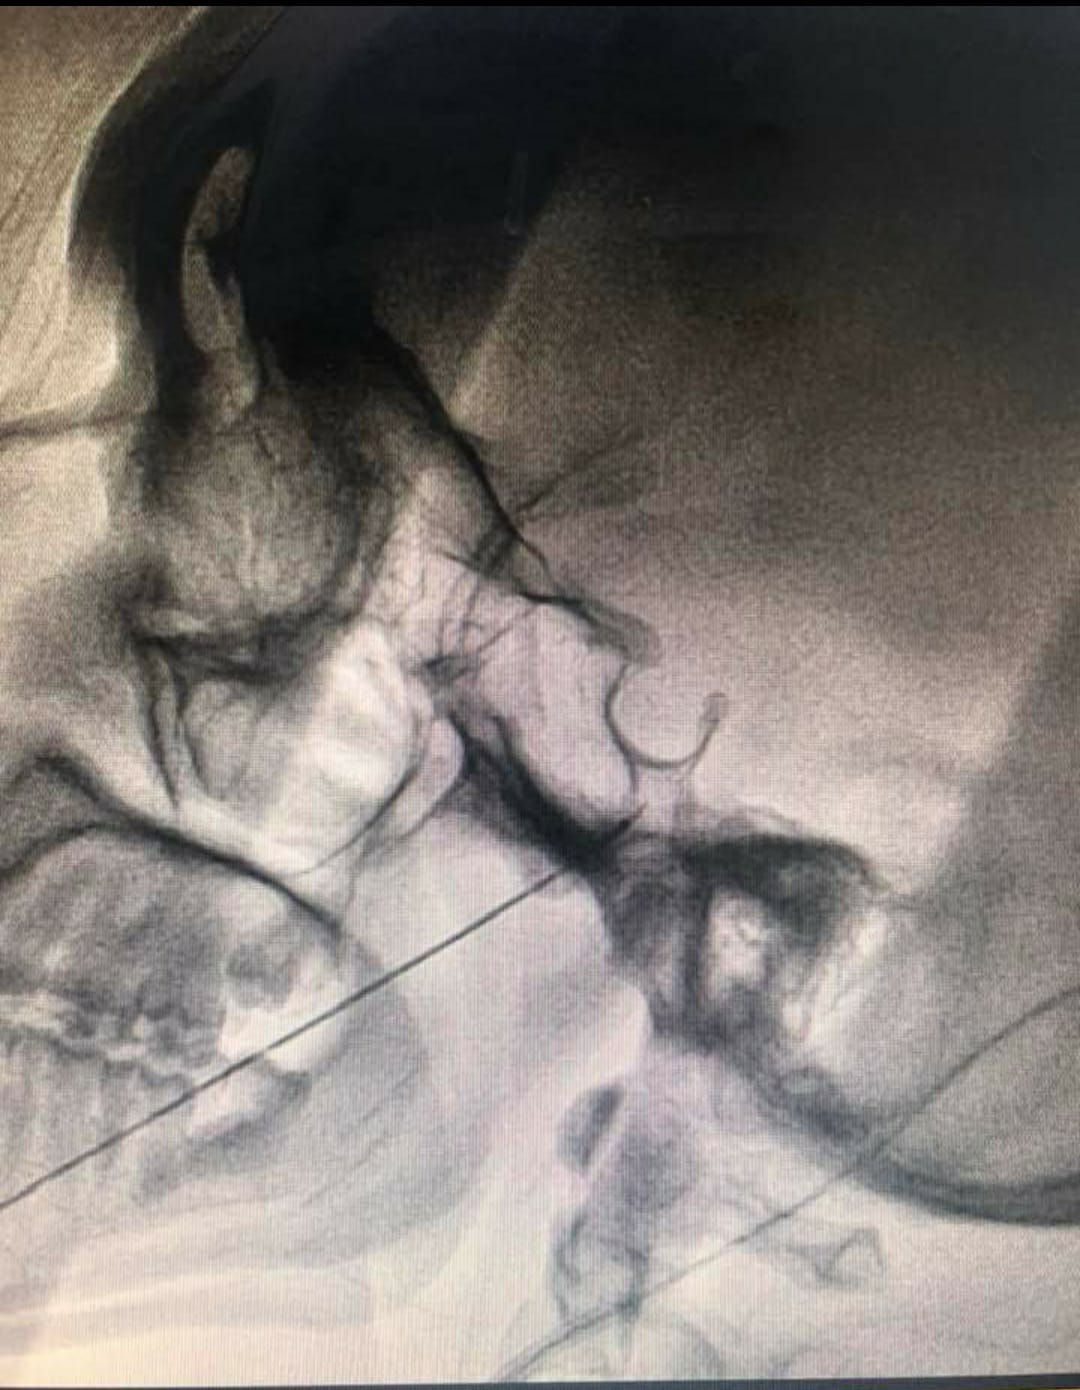

• Fluoroscopy guided Radiofrequency ablation of the Gasserian ganglion of Trigeminal nerve

• Balloon compression of the Gasserian ganglion of Trigeminal nerve